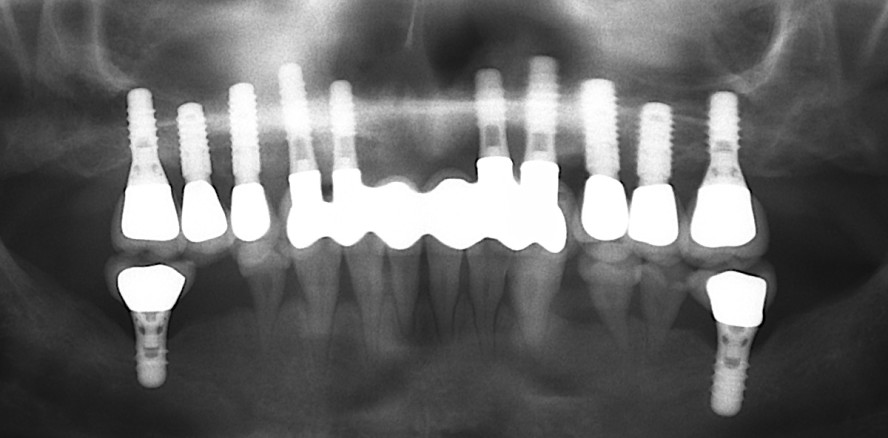

Foto: © Klinik für MKG-Chirurgie, Klinikum Stuttgart

Völlig hergestellte Kaufunktion und ästhetisch ansprechendes Ergebnis durch Einsatz von Zahnimplantaten

Im Alter von drei Jahren erkrankte die Patientin an einem bösartigen Tumor des Nasen-Rachenraumes und wurde als kleines Kind mit Strahlen- und Chemotherapie geheilt. Als Nebenwirkung dieser Tumor-Behandlung wuchs das Mittelgesicht des Mädchens nicht in gleichem Maße wie der restliche Körper. Auch die Zähne litten unter der Behandlung, bildeten keine vollständigen Wurzeln aus und gingen nach und nach verloren.

Mit aufwendigen Knochentransplantationen aus der Beckenregion und Implantation im Oberkiefer ist die heute 37-jährige Patientin vollständig wiederhergestellt.

Aufwendiger Knochenaufbau und neue Frontzähne auf Implantaten

Bereits im Jahr 1999 wurde in der Oberkieferfront eine extrem aufwendige Augmentation (Aufbau) mit Knochen vom Beckenkamm und anschließende Implantation im Frontzahnbereich (regio 13–23) durchgeführt, da es aufgrund der Vorerkrankung zum Verlust der Zähne und des Knochens kam. Zusätzlich war das Weichgewebe durch die Bestrahlung vorgeschädigt. Trotz dieser Extrembedingungen gelang es dem erfahrenen Stuttgarter MKG-Chirurgenteam um Prof. Weingart, durch Anhebung des Nasenbodens und Einbringung von Eigenknochen in dieser Region ein Fundament für eine neue „Zahnversorgung“ mit Implantaten zu schaffen. Über die Jahre konnten die Seitenzähne zunächst gehalten werden.

Im Laufe der Zeit zeigte sich aber, dass die Wurzeln nur noch „auf dem Zahnfleisch auflagen“ und lediglich durch eine Verblockung der Zähne hielten.

Kieferknochenaufbau und Implantate im Seitenzahnbereich

Daher mussten auch die Seitenzähne im Oberkiefer und teilweise im Unterkiefer entfernt und mit Implantaten ersetzt werden. Dies erfolgte unter anderem mit Einsatz von navigationsgestützten Techniken, im Seitenzahnbereich des Oberkiefers musste eine sogenannte Sinusaugmentation mit Knochen durchgeführt werden. Dabei wurde mit allen Vorsichtsmaßnahmen vorgegangen, die nach einer Bestrahlung des Knochens zu treffen sind. Bis zur letztendlich verbleibenden festsitzenden Versorgung der Implantate mit Kronen musste die Patientin eine herausnehmbare Prothese mit Gaumenabdeckung tragen, welches sie als junge Mutter sehr belastete. Umso glücklicher ist die Patientin nun über ihre vollständige prothetische Rehabilitation.